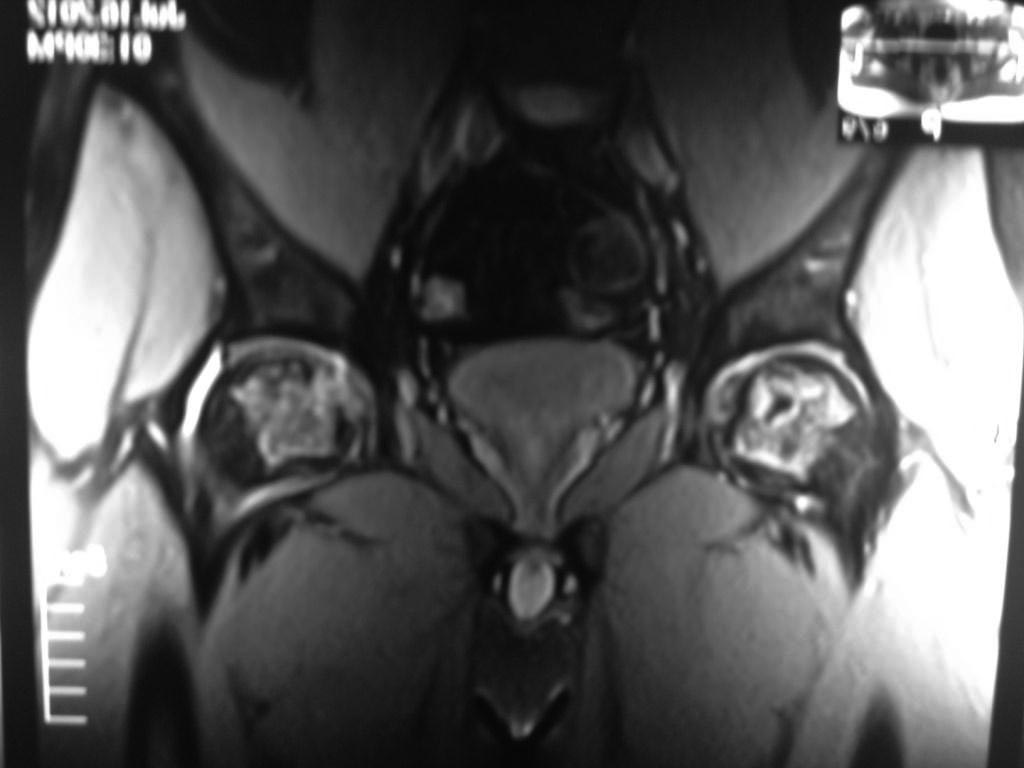

Возможно сомнения в диагностике связаны с нетипичной рентгенологической картиной. На снимке большая киста, которая расположена в центре головки, а при АВН начинается в верхней нагрузочной зоне. Отсутствует коллапс, сохранилась сферичность головки; не очень выраженный, но характерный признак "Crescent Sign".

Диффернциальную диагностику надо делать с доброкачественной кистой или метастазами. Но двухсторенная киста встречается очень редко, и киста в шейке распологается более дистально, чем при АВН. Гетерогенная картина головки немного напоминает метастаз, но без первичной опухоли и затяжной характер течения заболевания снимает подозрение на злокачественный процесс.

При наличии коллапса диагноз устанавить очень легко. Сканирование с изотопами тоже хороший метод исследования, который покажет "холодные" участки, окруженные "теплыми" зонами. Исследование в 25% дает погрешность, и поэтому на сегодня МРТ является "золотым стандартом" исследования. Пункция не помешает, но мне кажется, что здесь по классификации Ficat преколлапсный, т.е. вторая степень АВН.